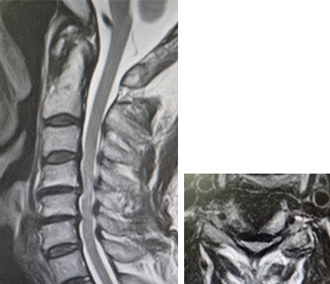

頚椎症性脊髄症・神経根症・頚椎椎間板ヘルニア

せぼね(脊椎)は7個の頚椎、12個の胸椎、5個の腰椎と仙椎から構成されます。腰椎は主に5つの骨と、間にあるクッションのような椎間板、また神経組織が通っている脊柱管から成り立っています。頚部の神経組織は、脊髄と枝分かれする神経根から構成されています。頚椎症性脊髄症は、骨の変形や椎間板の膨隆、あるいは不安定性などにより、頚椎の脊柱管の狭小化が生じることで頚髄が圧迫される病気です。脊柱管が比較的狭い日本人は欧米人に比べて発症しやすい特徴があります。また、頚椎症性神経根症は椎間板の膨隆や骨棘(骨のトゲ)によって神経根が圧迫される病気です。

局所の症状として、頚部や背部の痛み、また肩こりなどの症状が出やすいです。脊髄が障害されると、手指の巧緻運動障害(箸が持ちづらい、字が書きづらい、ボタンが上手くはめられない)、痙性歩行(ふらつき・つまずきやすい・歩行がぎこちない)、膀胱直腸障害(頻尿・残尿感)などの症状が生じます。神経根が障害された場合には、どちらか一方の腕や肩甲骨の裏側に放散する痛みやしびれ、力が入りにくいといった症状が生じます。

せぼねの変形や椎間板の傷み具合、すべりや不安定性の有無、脊髄の圧迫の程度、またせぼね全体のバランスなどを見るためにX線検査やCT検査、MRI検査などを行います。進行例では脊柱管の狭さをより詳しく評価するために入院して脊髄造影検査を行う場合があります。どの神経が痛みの原因となっているかを明らかにするため、あるいは除痛目的に神経根に直接麻酔薬を注入する選択的神経根ブロックを行う場合もあります。成人期では血管性のしびれがないか評価するために両手足の血圧を測ったり、骨粗鬆症の有無を評価するために骨密度検査を行うこともあります。